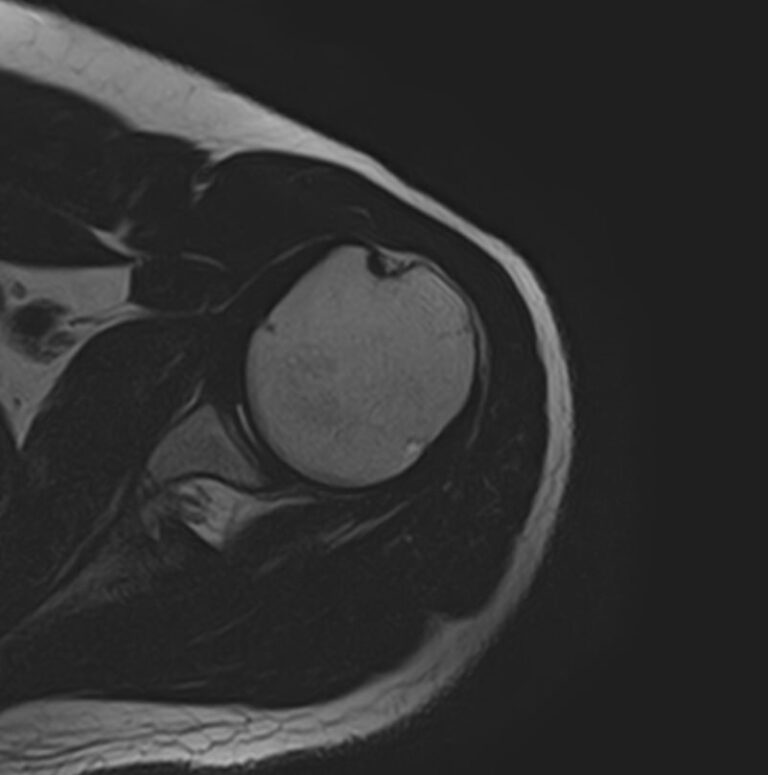

Метод МРТ позволяет оценить состояние всех анатомических областей плечевого сустава,  включая костную структуру, суставную капсулу, полость сустава с выстилающей его синовиальной оболочкой, связки, сухожилия, мышцы и окружающие мягкие ткани.

В клинике «Доступная медицина» исследование проводится на современном высокопольном томографе закрытого типа TOSHIBA VANTAGE TITAN 1,5 Тесла с превосходной  разрешающей способностью, которая обеспечивается высокой индукцией магнитного поля. Аппарат выполняет сканирование послойно в различных плоскостях и на основе этого создает 3D-изображения с высочайшей точностью и достоверностью, что позволяет эффективно ставить диагноз и назначать необходимое лечение.